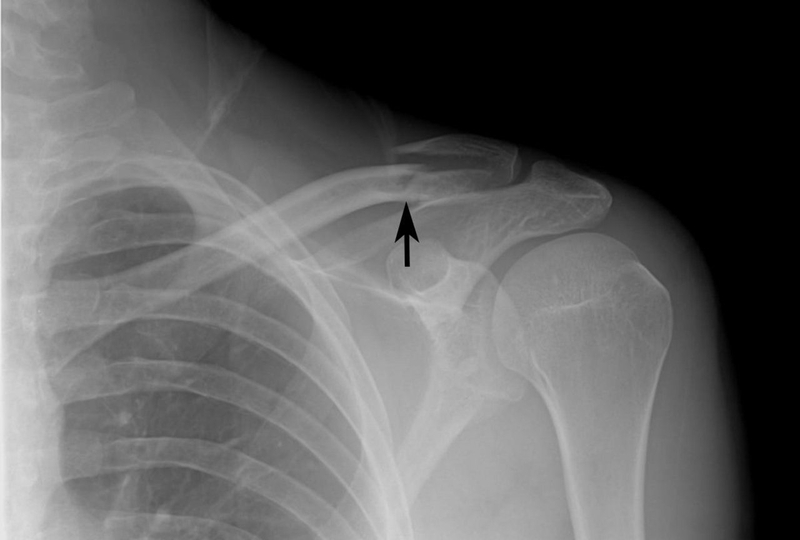

Phương pháp chẩn đoán hình ảnh

Nếu như việc xét nghiệm máu có thể giúp bác sĩ chẩn đoán được chứng đau nhức xương khớp có liên quan đến viêm khớp vai hay không thì thông qua việc chẩn đoán hình ảnh bằng tia X-quang, bác sĩ có thể phân loại được nhóm bệnh viêm khớp ở trẻ nhỏ và xác định được tình trạng thương tổn tại các khớp.

Bên cạnh đó, việc chụp X-quang cũng tạo nên nguồn tư liệu quan trọng để các bác sĩ có thể theo dõi được sự phát triển của hệ xương khớp ở trẻ sau này.

Viêm khớp vai ở trẻ em: Nguyên nhân, triệu chứng và cách chẩn đoán3 Chụp X -quang